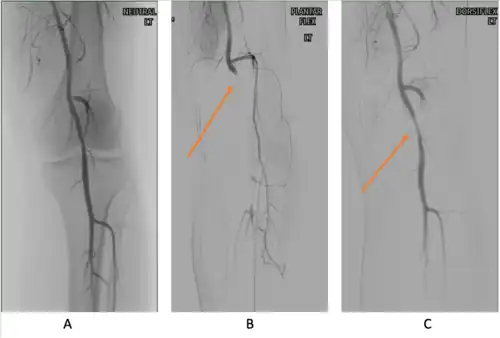

Provocative maneuvers can be used to improve visualization of PAES on the images.[25] The patient is initially positioned supine with the legs straight, and then instructed to forcefully plantar-flex. A plantarflexion force of 0 to 70 percent maximum has been shown to maximize the sensitivity and specificity for PAES diagnosis.[25] The DU can be a quick, inexpensive, and noninvasive initial screening for PAES. Flow velocities in the popliteal artery will increase, as the popliteal artery is compressed, which is reflected on the DU. If DU is negative but there is still strong suspicion for PAES, MRA or CTA with provocative maneuvers are needed as follow-up imaging. MRA would demonstrate a focal occlusion or narrowing of the mid-popliteal artery, post-stenotic dilatation, or aneurysm of the distal popliteal artery. If MRA or CTA is[13] non-conclusive, DSA may be used as a further option with a high sensitivity (> 97%) for PAES diagnosis.[23]

Additionally, functional PAES in which the gastrocnemius hypertrophy causes arterial compression during exercise can be best evaluated with dynamic CT.[23] For dynamic CT, initial images are taken with the patient still. Further images are taken following a series of provocative maneuvers.